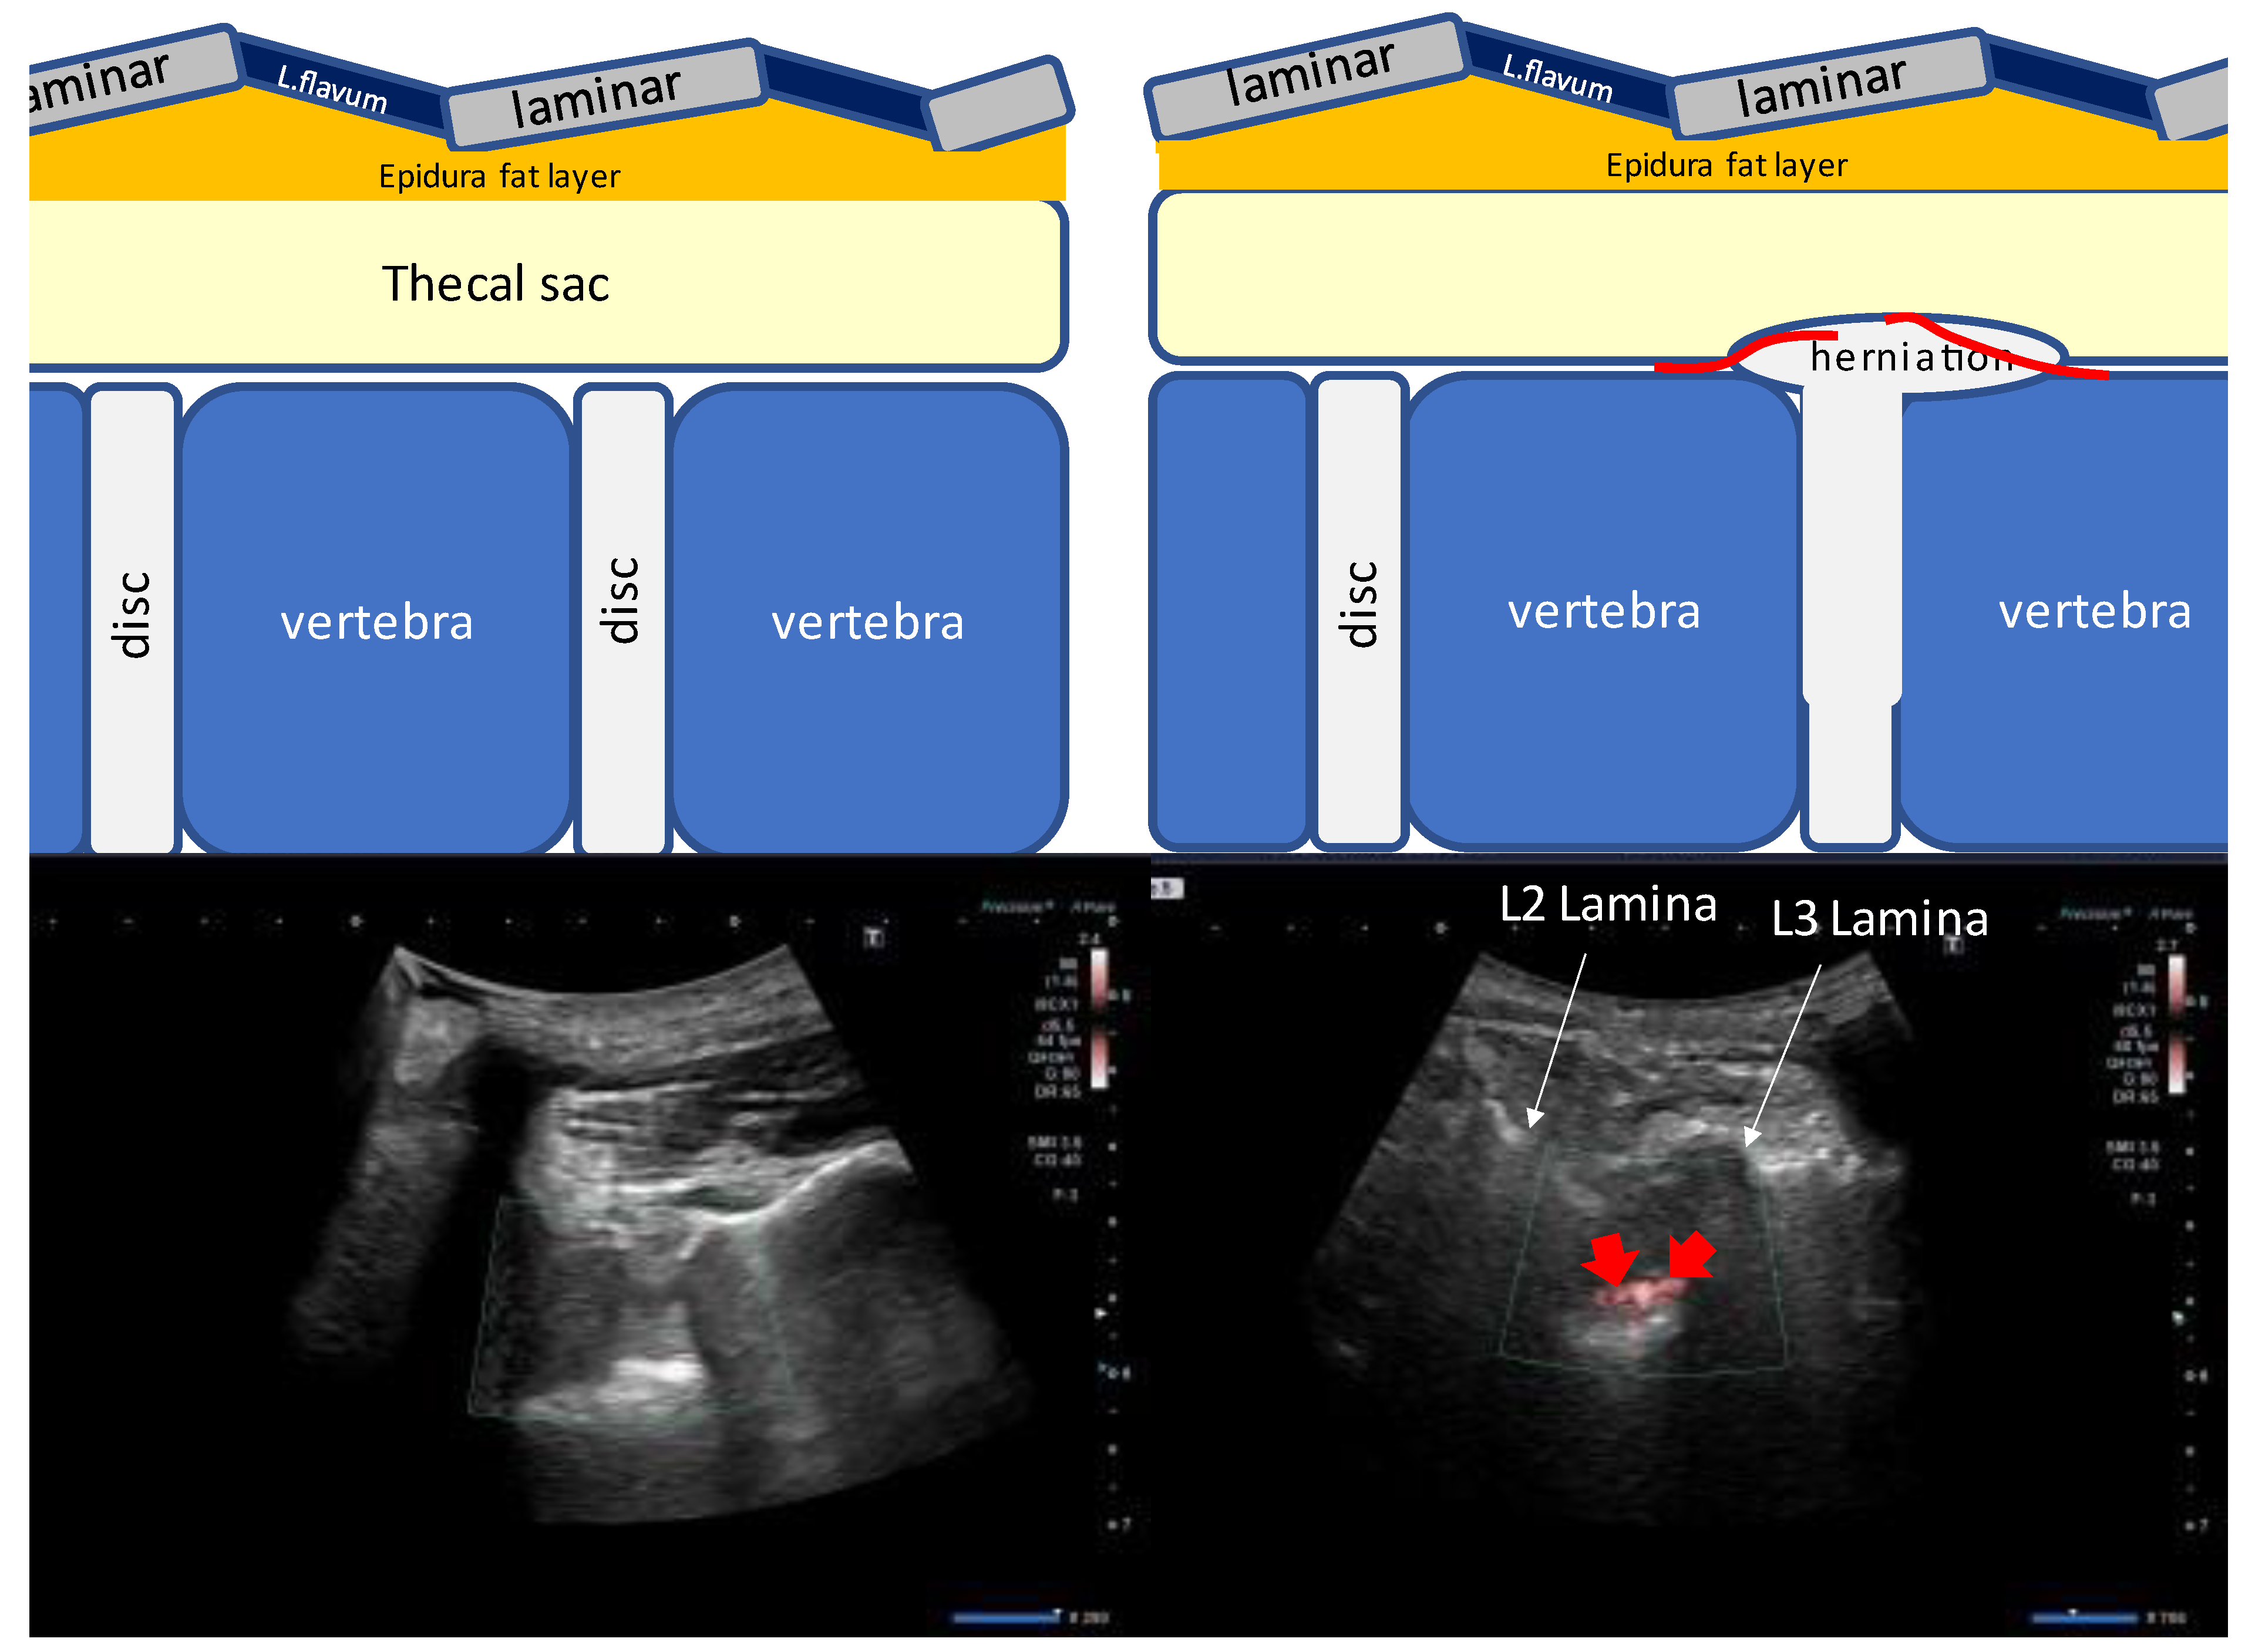

- Guide the needle into the ligamentum flavum.

- Advance the needle to the depth where resistance disappears (LOR).

- Confirm that the site of LOR is the epidural space.

- Confirm that the drug solution is appropriately distributed into the epidural space.